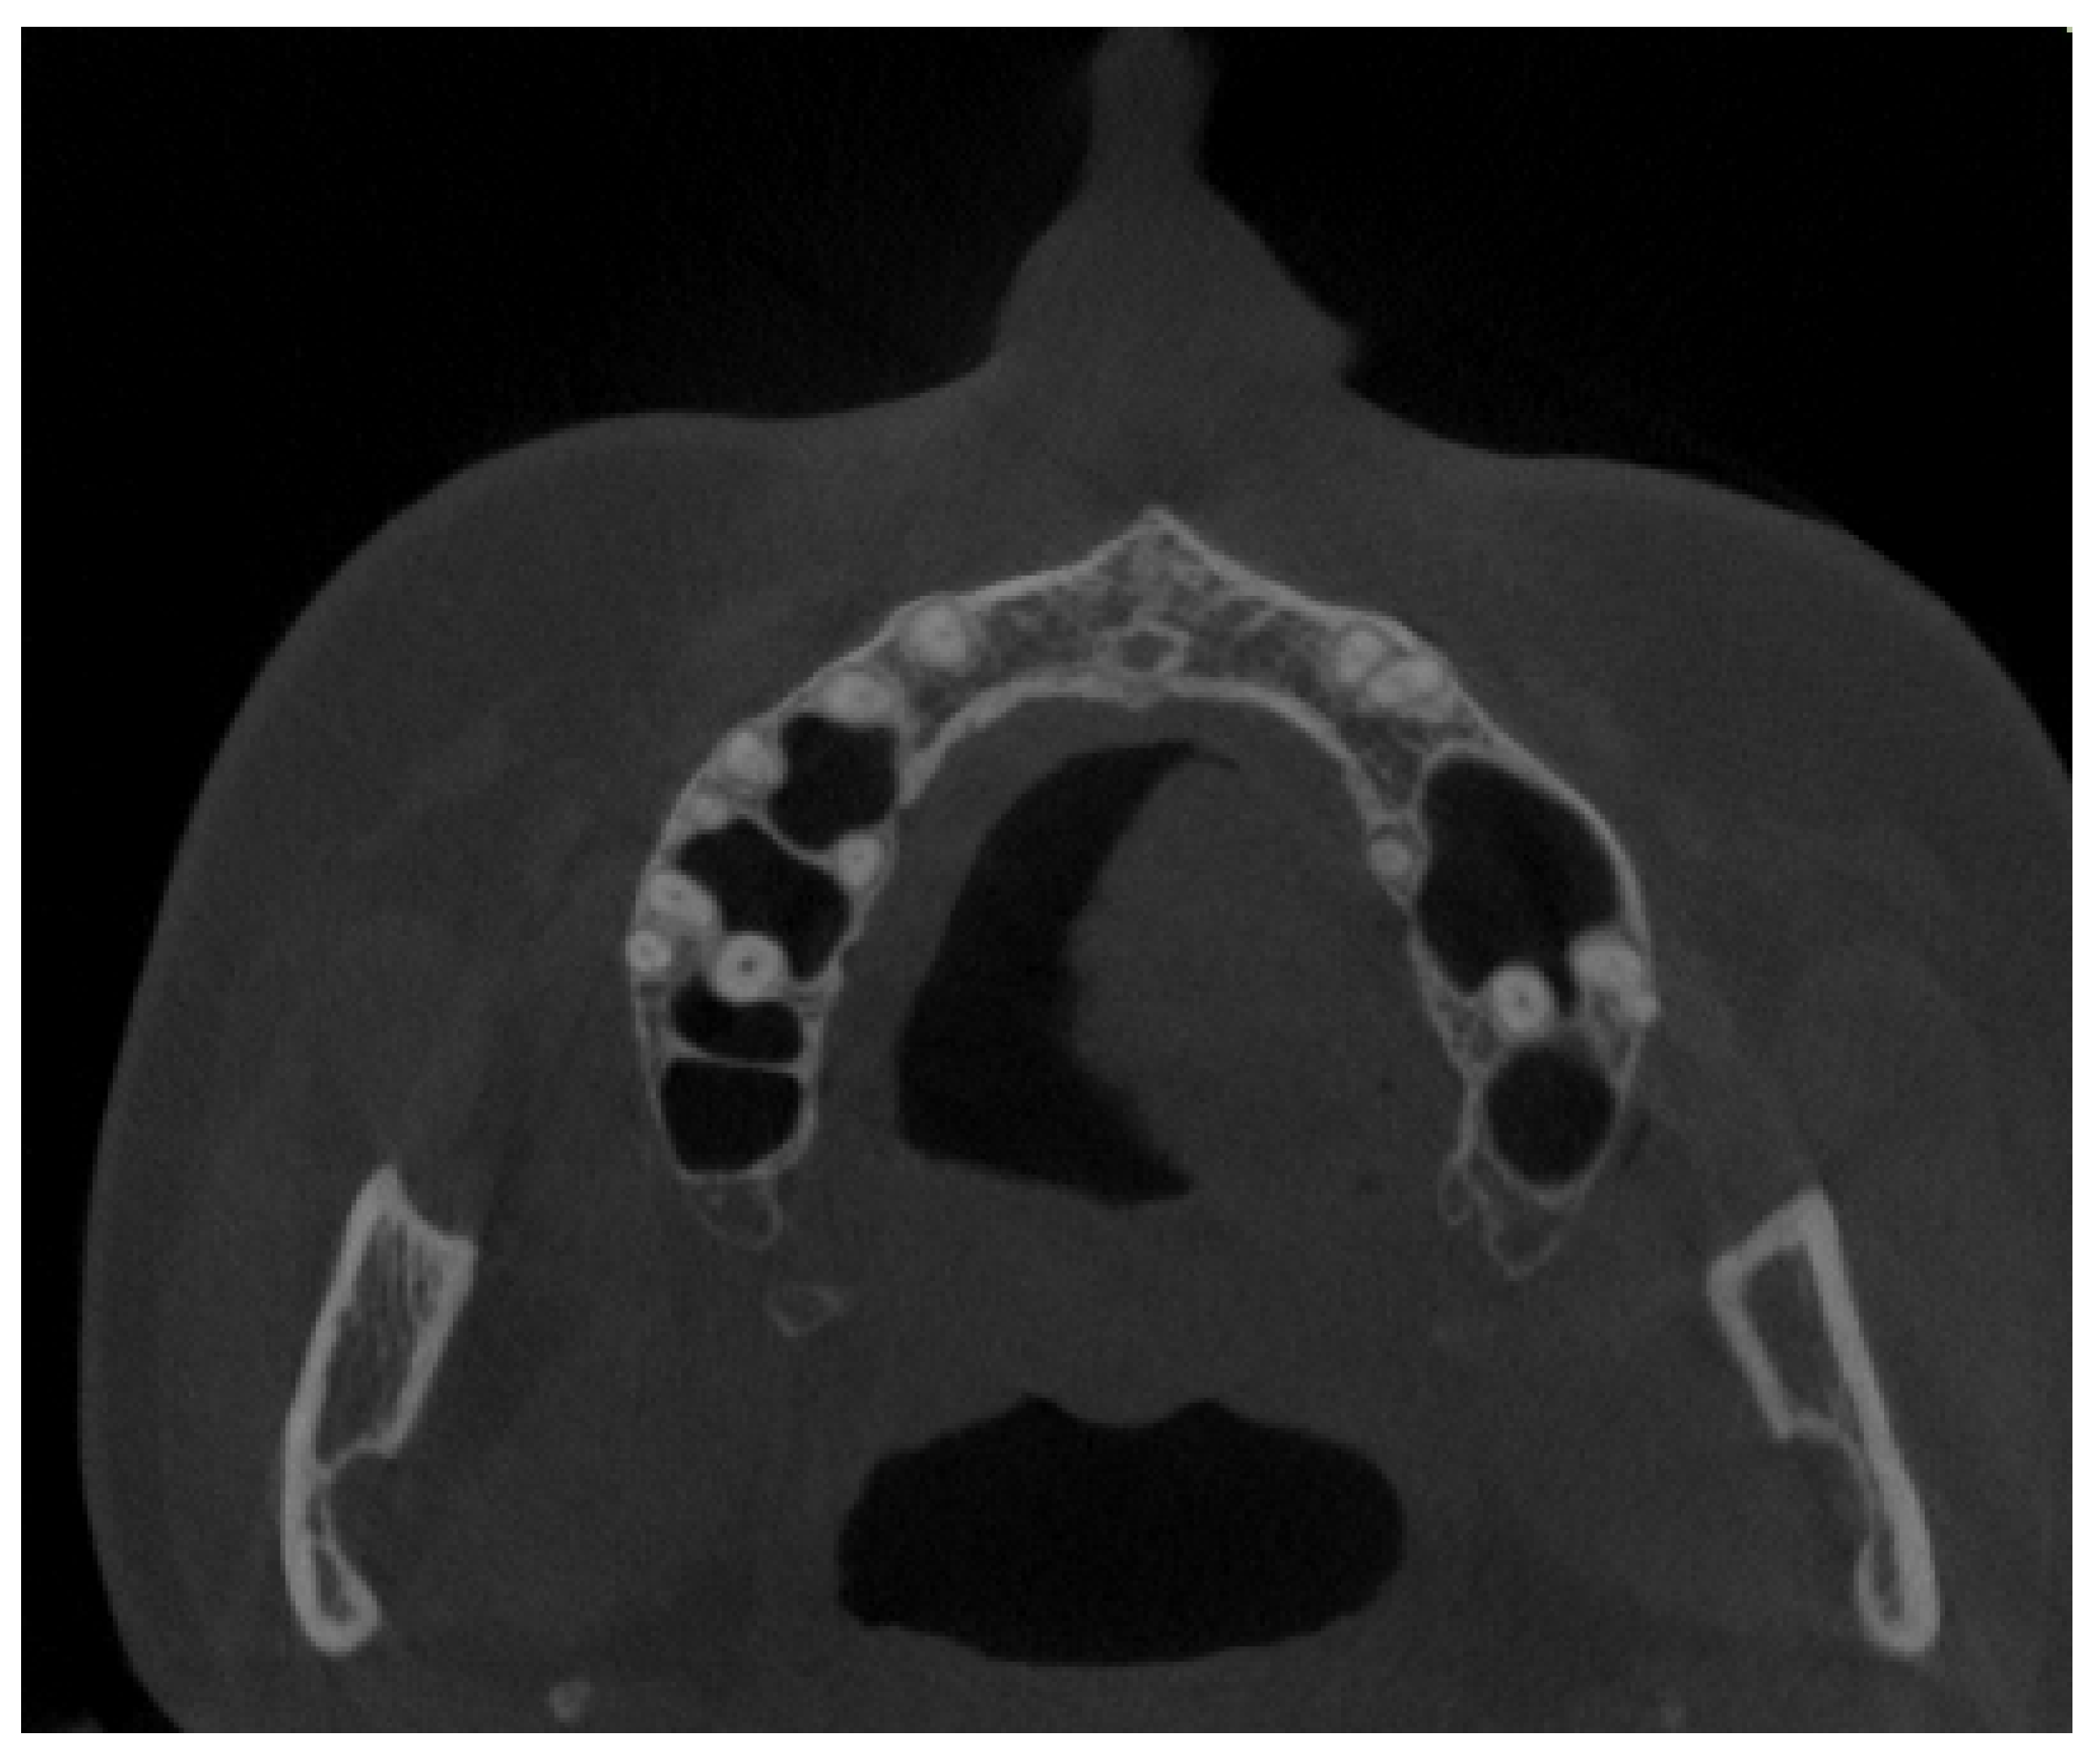

2. Material and Methods

2.2. Cone Beam Computed Tomography Characteristics

| Dental status: | 0.232 | |||

| Full dentition | 103 (85.83) | 66 (88.00) | 37 (82.22) | |

| Partial dentition | 15 (12.50) | 7 (9.33) | 8 (17.78) | |

| Full edentulism | 0 (0.00) | 0 (0.00) | 0 (0.00) | |

| Partial edentulism | 2 (1.67) | 2 (2.67) | 0 (0.00) | |